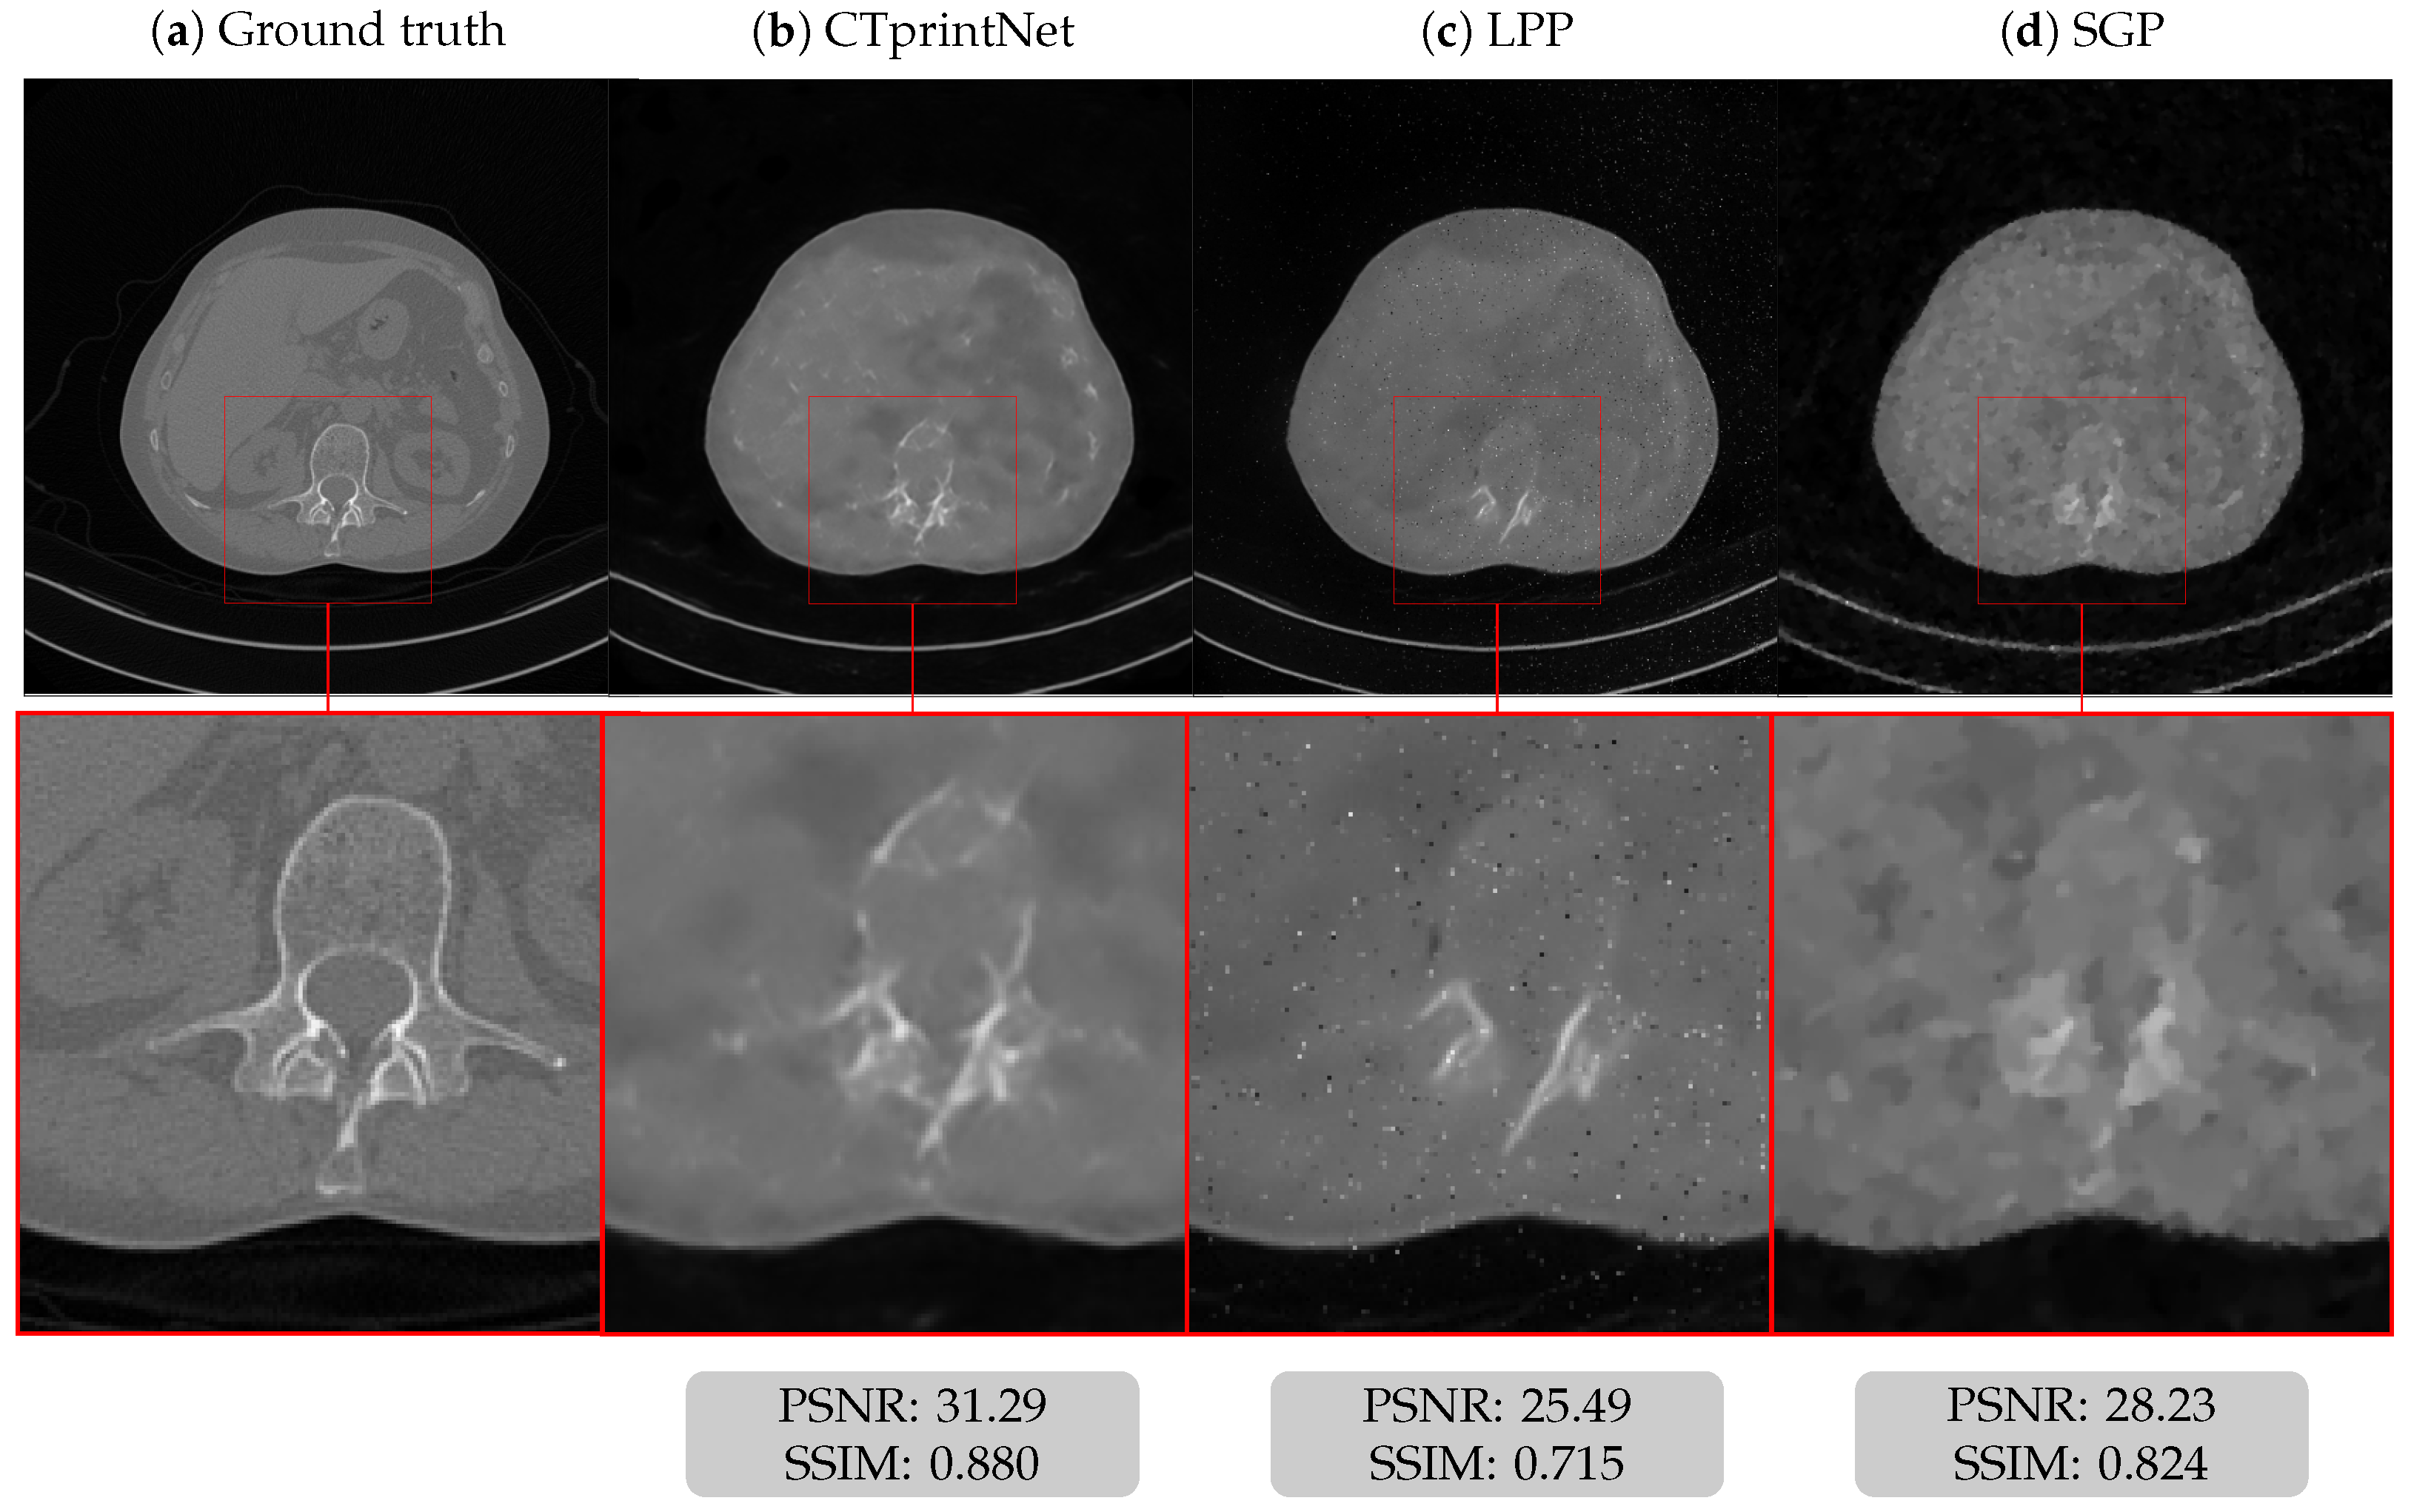

5.1. Results on a Synthetic Dataset

5.3. Results on a Realistic Dataset